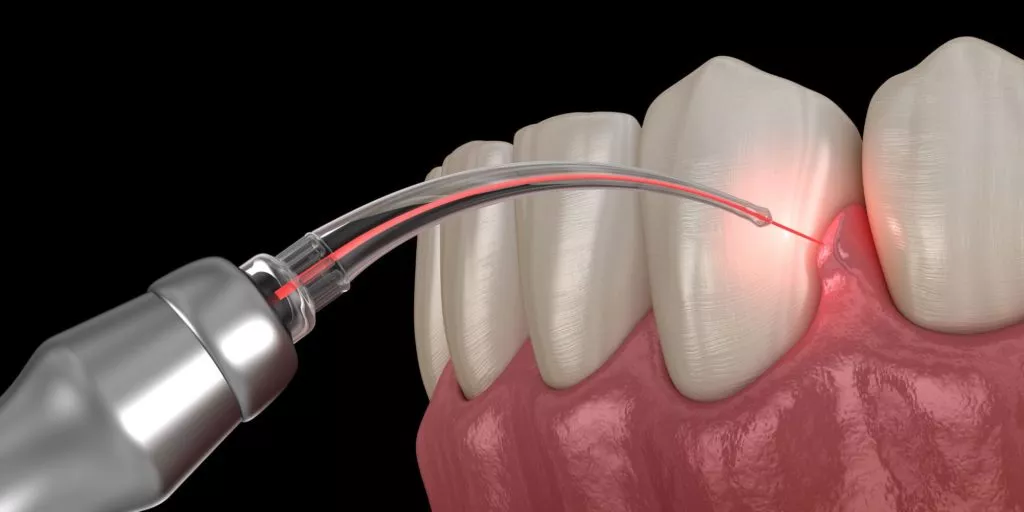

Laser Dentistry

Advanced Laser Therapy for Healthier Gums and a Brighter Smile

At GS Dental Care, we specialize in providing exceptional dental laser treatments using state-of-the-art technology, ensuring that you receive the best possible care. Laser dentistry is a minimally invasive treatment for addressing periodontal and gum issues, crown lengthening, and laser-assisted teeth procedures.

Laser Periodontal Therapy

Treats gum disease by removing bacteria and infected tissue.

Laser Frenectomy

Corrects tongue-tie or lip-tie with a quick and painless laser procedure.